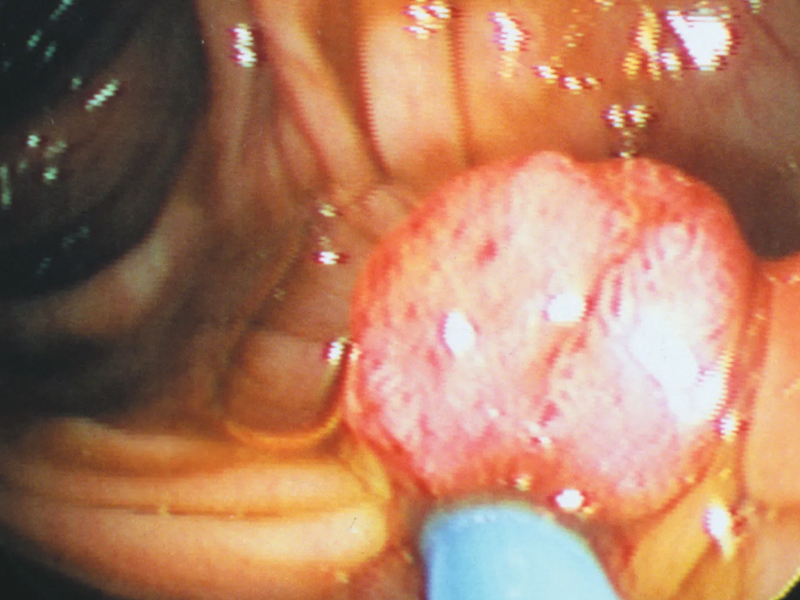

仔細看圖,我們會觀察到,前列腺位於膀胱下方,圍繞著尿道的起始部,前方為恥骨聯合(圖中白色部分,男性朋友可以自己觸摸身體,陰莖上方的骨性結構即為恥骨聯合),而後方有直腸 (這也可以解答很多病人的另一個疑問:為什麼大夫手指伸進肛門能摸到我的前列腺?)。此外,我們發現前列腺幾乎位於陰莖根部,當進行騎車、騎馬運動時,前列腺很容易因為與所騎物體的接觸而摩擦、充血,產生炎症。 (某研究證實,專業騎自行車運動員患前列腺癌的比例更高)